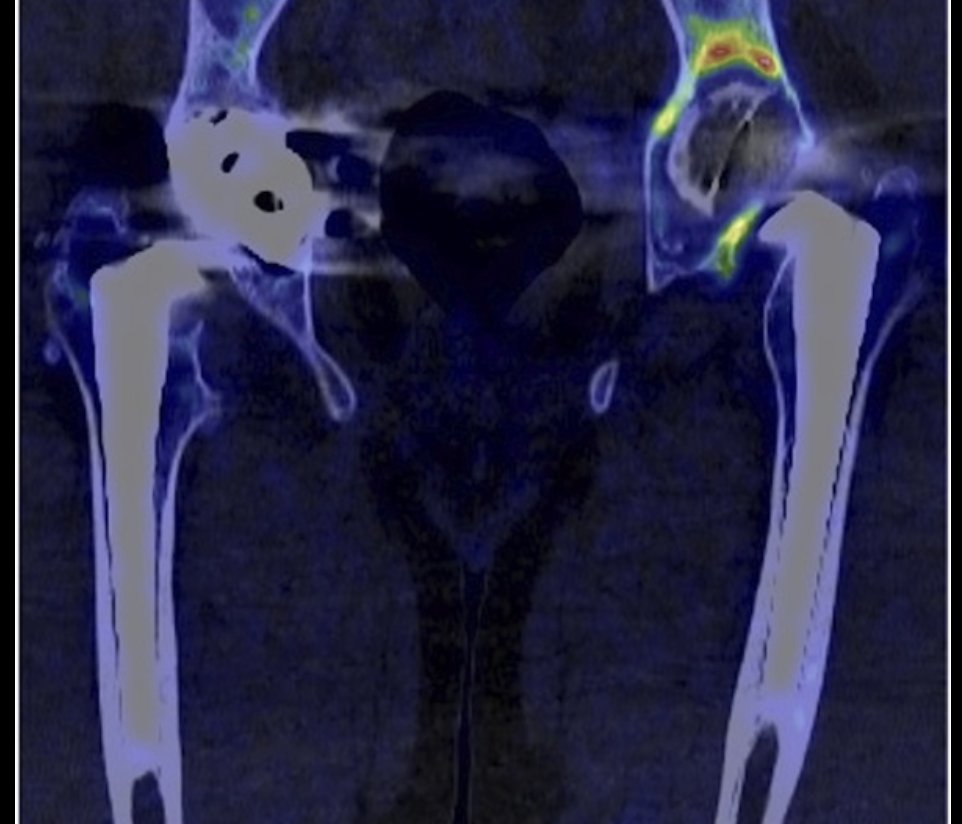

46 #Revision THA B3 with insufficient isthmus Cone-in-cone + distal interlocking at 4yrs 42 bony + 4 fibrous ingrowth stem The Bone & Joint Journal #hipreplacement buff.ly/5BOGCp5